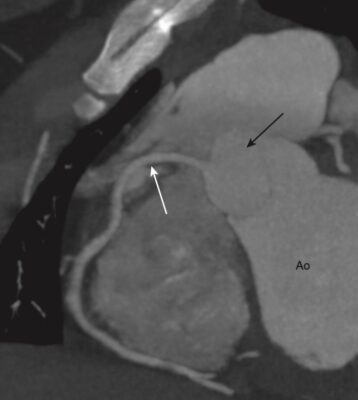

Chụp CT mạch vành (CCTA) — Giải phẫu bình thường

CCTA có độ chính xác khá tốt so với chụp động mạch vành xâm lấn (đặt thông), vẫn là tiêu chuẩn tham chiếu trong nghiên cứu động mạch vành.

Có nhiều biến thể của giải phẫu động mạch vành bình thường. Ở đây chỉ mô tả phân nhánh phổ biến nhất (Hình 12).

Hai động mạch vành chính là động mạch vành trái và phải.

- Động mạch vành trái (LCA) phát sinh từ đỉnh động mạch vành trái tại van động mạch chủ. Nó phân chia gần như cùng một lúc thành động mạch mũ và động mạch gian thất trước (nhánh xuống trước trái (LAD). LAD, sau đó tạo ra các nhánh chéo (diagonal) và các nhánh vách (septal). Động mạch mũ có các nhánh biên (marginal) (Hình 13).

- Động mạch gian thất trước (LAD) đi trong rãnh liên thất trước và tiếp tục đến đỉnh tim. Nó cung cấp hầu hết tâm thất trái và cả bó nhĩ thất (AV), phần trước của vách với các nhánh vách và thành trước của tâm thất trái với các nhánh chéo (Hình 14).

- Động mạch mũ nằm giữa nhĩ trái và thất trái và cung cấp các mạch rìa tới thành bên của tâm thất trái.

- Động mạch vành phải (RCA) xuất phát từ xoang động mạch chủ, chạy giữa nhĩ phải và thất phải đến phần dưới của vách ngăn (Hình 15).

- Ở hầu hết mọi người, nhánh đầu tiên của RCA là nhánh nón ( conus branch) cung cấp cho đường ra của tâm thất phải. Ở hầu hết mọi người, nhánh thứ hai của RCA là động mạch nút xoang. Các nhánh tiếp theo là các nhánh chéo cấp máu cho thành trước của thất phải.

- Nhánh bờ (acute marginal branch, AM) lớn cấp máu cho thành bên của thất phải và chạy dọc theo bờ của thất phải trên cơ hoành. RCA đi tiếp ở phía sau rãnh nhĩ thất và cho một nhánh tới nút nhĩ thất.

- Ở hầu hết mọi người, động mạch gian thất sau (xuống sau, PDA) là một nhánh của RCA. PDA cấp máu cho thành dưới của tâm thất trái và phần dưới của vách ngăn.